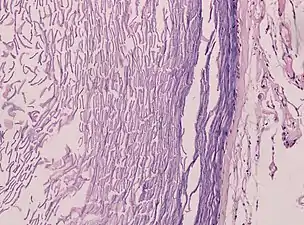

Histopathologie, montrant un épithélium pavimenteux stratifié kératinisant et une lumière contenant des débris de kératine

Histopathologie montrant l'épithélium et la kératine lamellaire (à gauche)